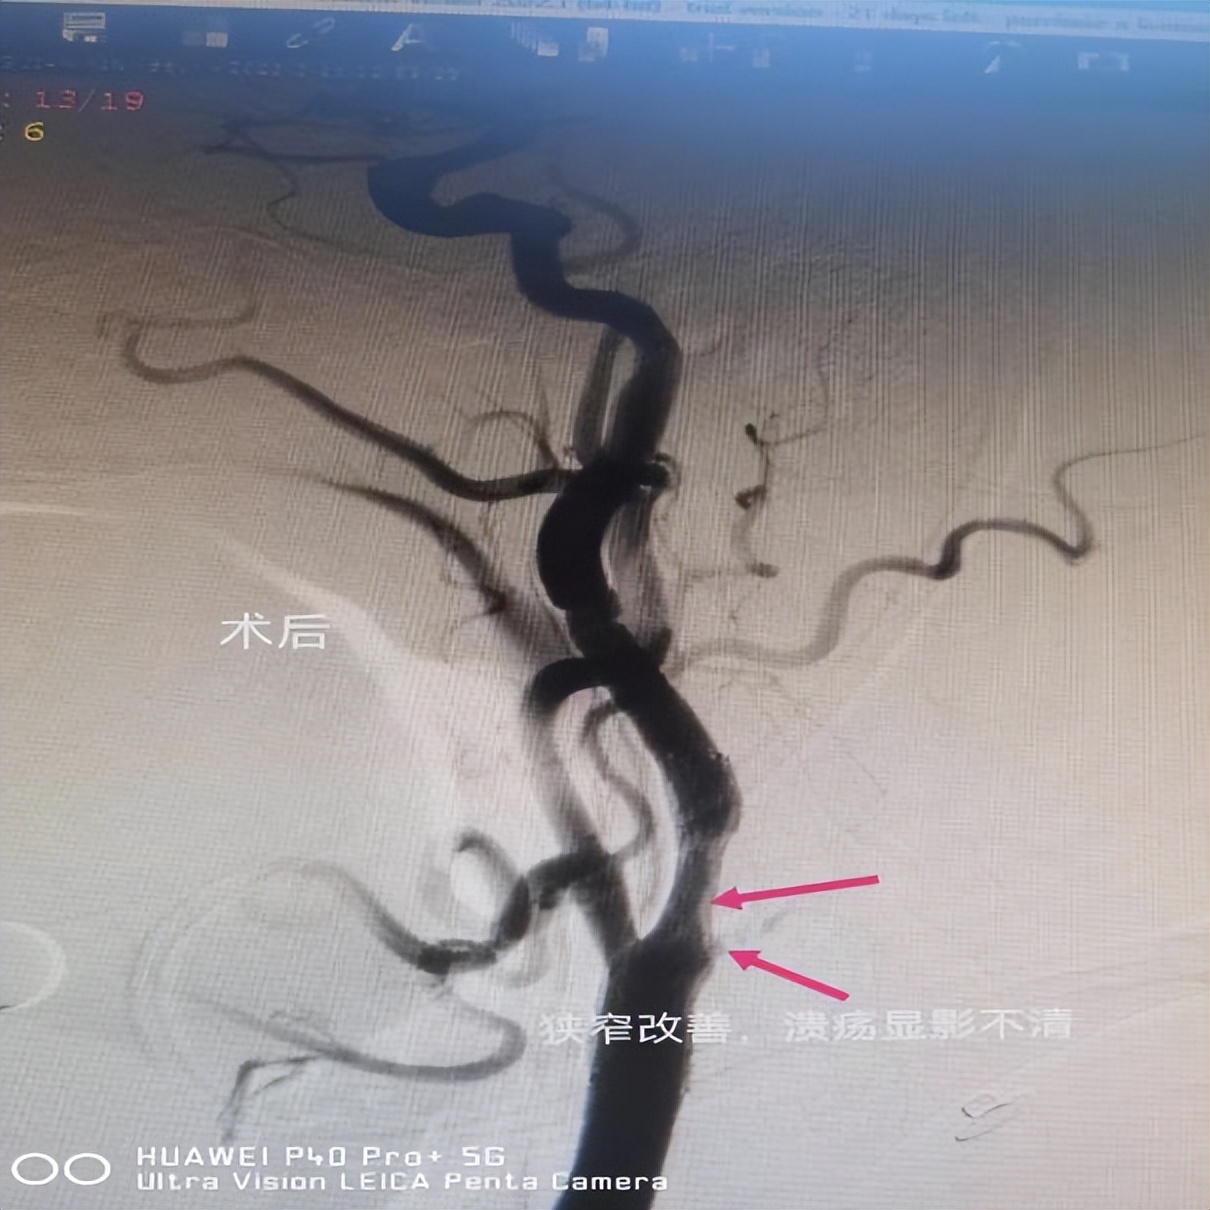

病例二: 右侧颈内动脉起始部位狭窄伴溃疡斑块球囊扩张+支架植入术

患者男性,66岁,以“左侧肢体活动不灵24小时”之主诉入院,入院诊断为急性脑梗死。脑血管造影提示右侧颈内动脉起始部位狭窄(狭窄率约60%)伴溃疡斑块形成,综合评估后在局部浸润麻醉下行右侧颈内动脉起始部位狭窄伴溃疡斑块球囊扩张+支架植入术。手术过程顺利,术后造影见狭窄明显解除,术后患者未诉不适。